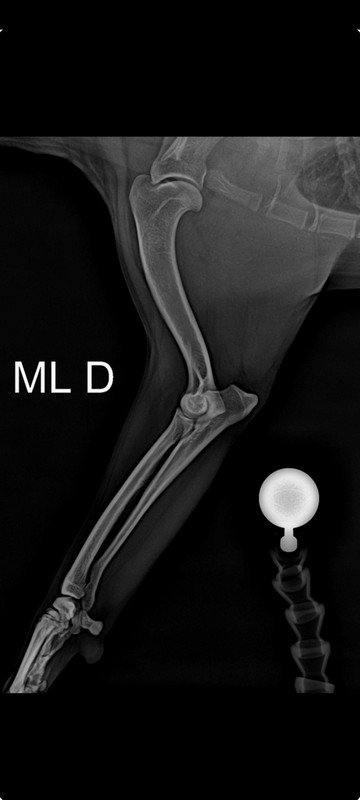

Raio x veterinário

Raio x veterinário é um dos exames mais comuns e importantes na prática clínica veterinária. Ele permite visualizar estruturas internas do corpo dos animais, sendo essencial para o diagnóstico de diversas condições de saúde, como fraturas, lesões, tumores, alterações pulmonares, entre outras.

A realização de raio x veterinário traz inúmeros benefícios para a saúde do seu pet. Além de ser uma ferramenta fundamental para identificar problemas de saúde, o exame também auxilia no acompanhamento de tratamentos, na prevenção de doenças e na manutenção da qualidade de vida do animal.

Existem diversas situações em que a realização de raio x veterinário pode ser indicada, como em casos de trauma, dor crônica, dificuldade respiratória, alterações no sistema digestivo, entre outros sintomas.